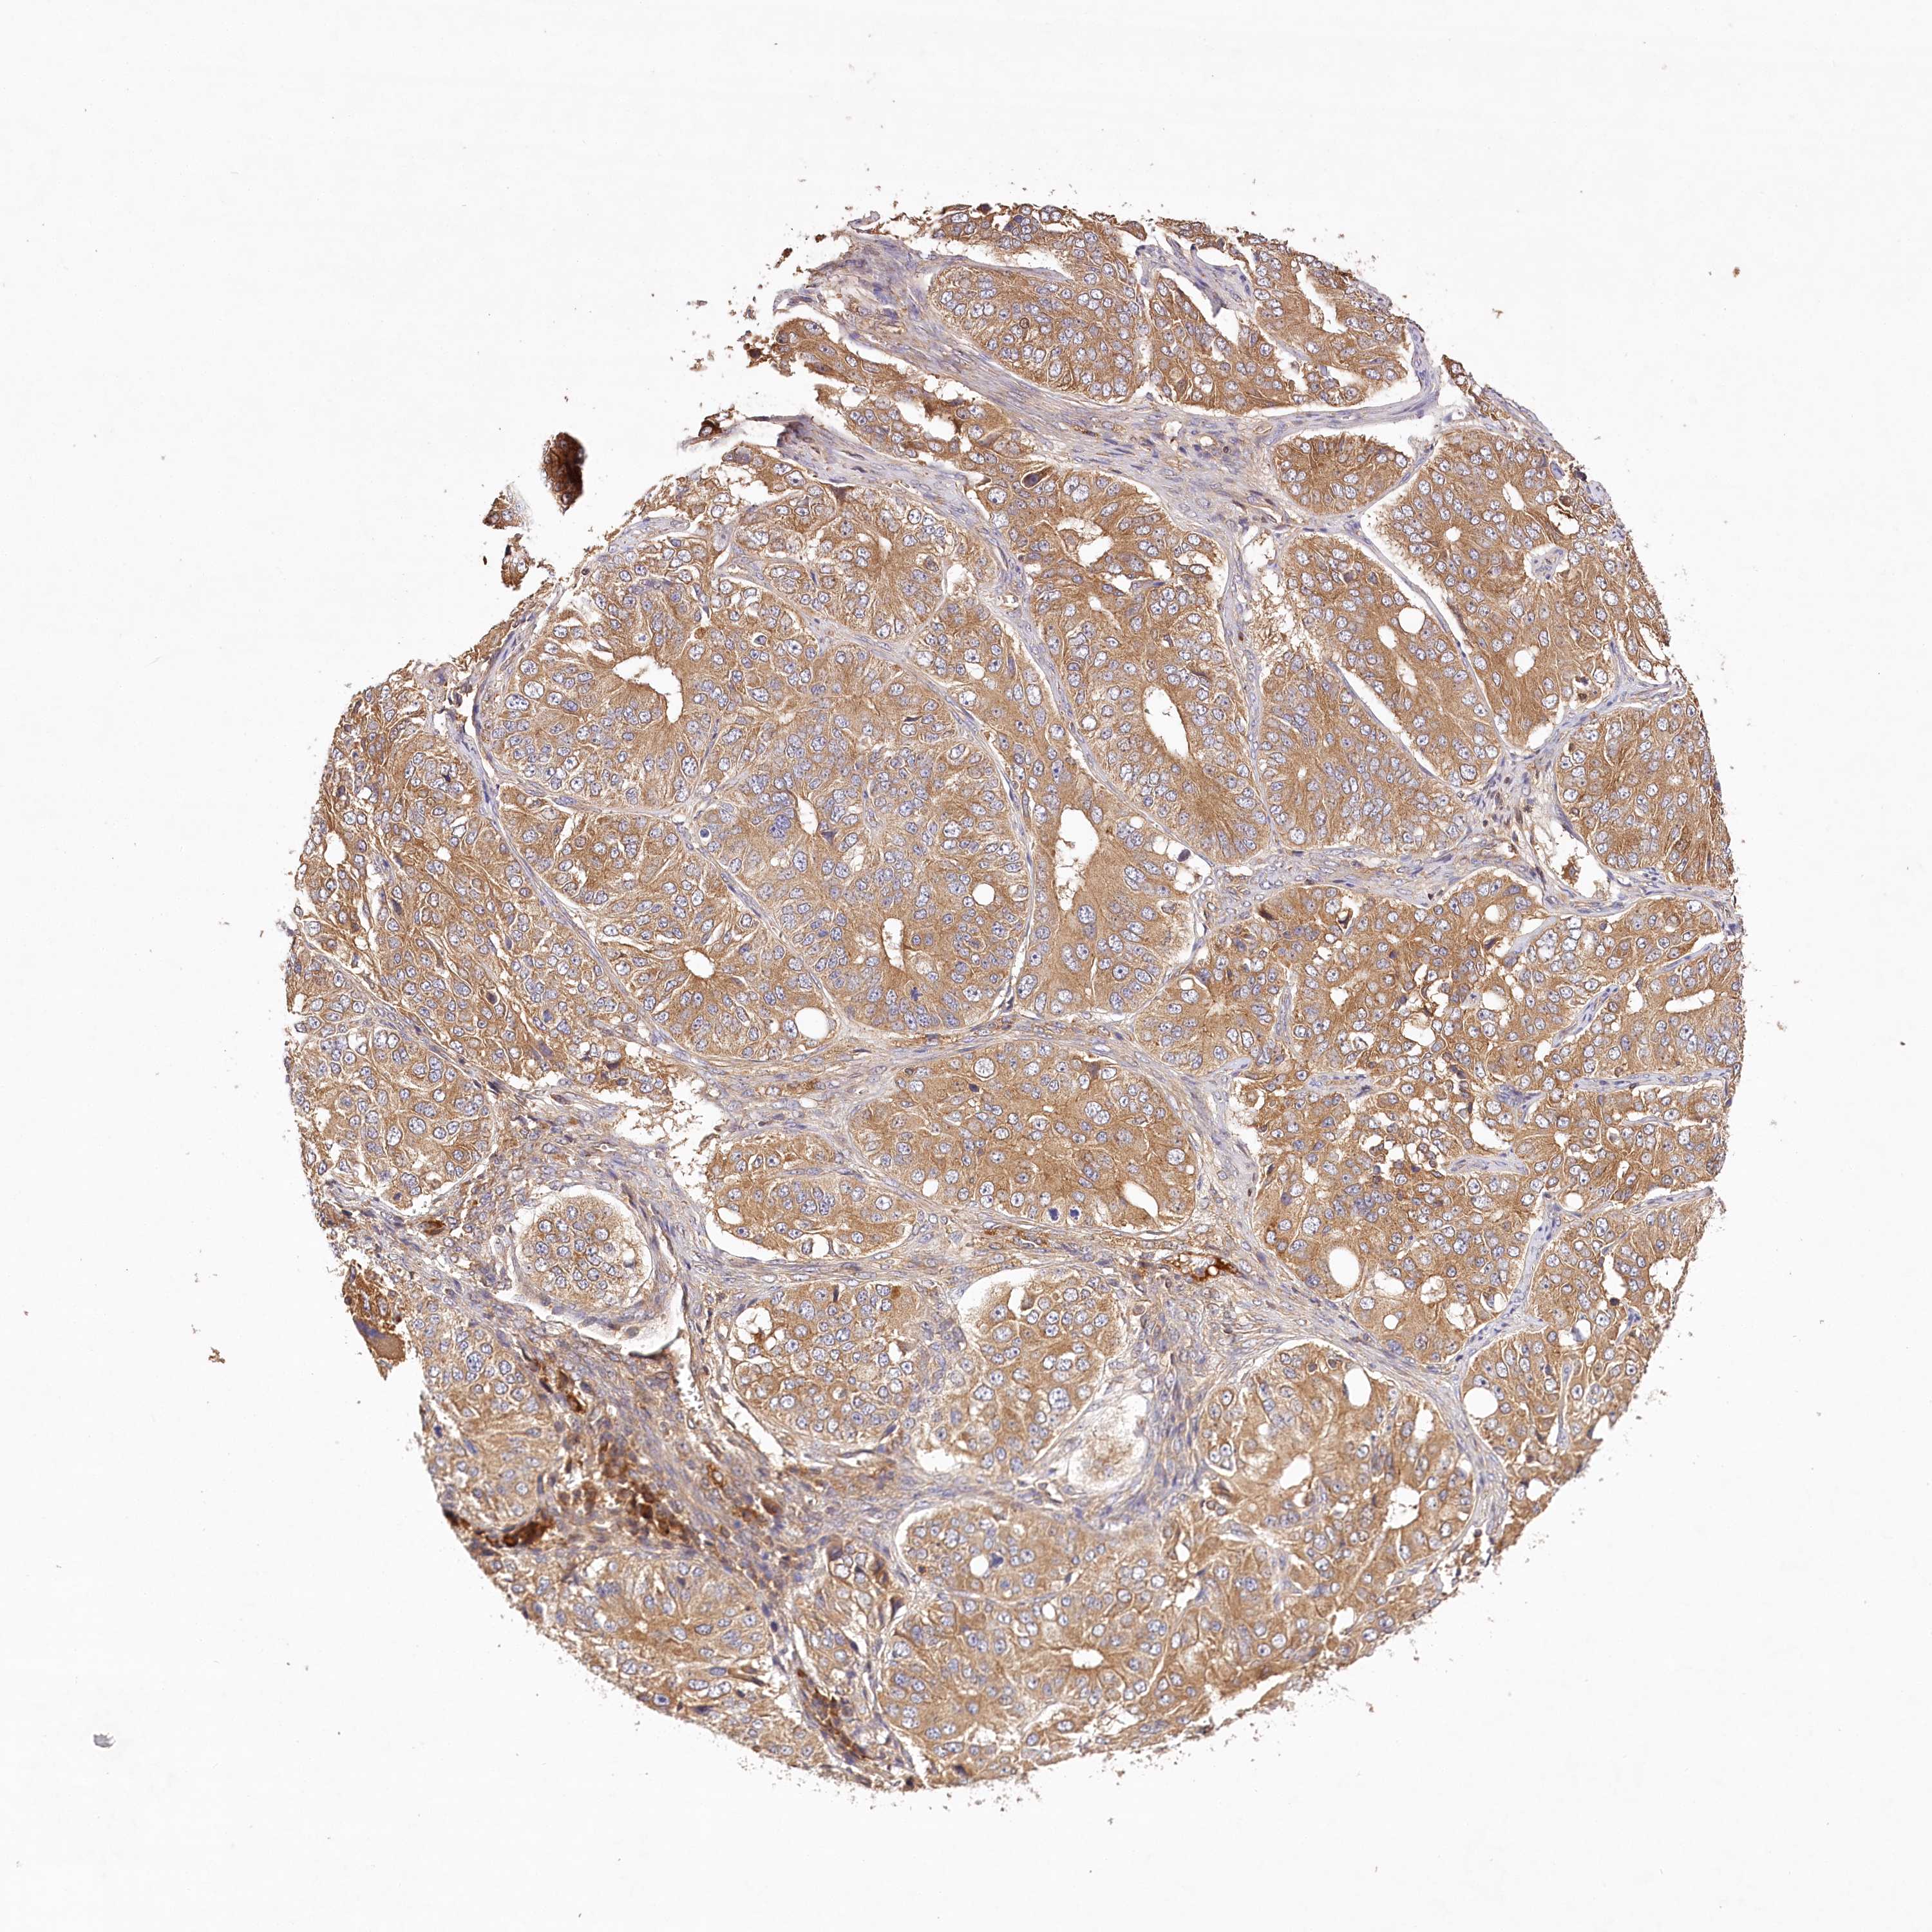

OVARIAN CANCER - Protein expressioni

A mouse-over function shows sample information and annotation data. Click on an image to view it in a full screen mode. Samples can be filtered based on level of antibody staining by selecting one or several of the following categories: high, medium, low and not detected. The assay and annotation is described here.

Note that samples used for immunohistochemistry by the Human Protein Atlas do not correspond to samples in the TCGA dataset.

Antibody stainingi

Antibody staining in the annotated cell types in the current human tissue is reported as not detected, low, medium, or high, based on conventional immunohistochemistry profiling in selected tissues. This score is based on the combination of the staining intensity and fraction of stained cells.

Each image is clickable and will lead to virtual microscopy that enables deeper exploration of all samples and also displays staining intensity scores, fraction scores and subcellular localization as well as patient and tissue information for each sample.

Antibody HPA032060

Antibody HPA032062

Antibody CAB034116

Staining

High

Medium

Low

Not detected

Cystadenocarcinoma, serous, NOS

Carcinoma, endometroid

Cystadenocarcinoma, mucinous, NOS

Carcinoma, NOS